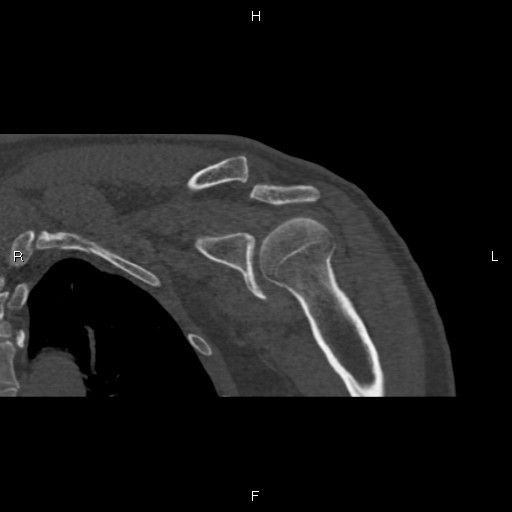

主诉:摔伤后左肩疼痛伴活动受限20天。 病史:患者入院前20天不慎摔伤,左肩不能活动,遂来我院急诊,摄片示左肩锁关节脱位,入院治疗。

查体:左锁骨外端突出,未见明显淤血,局部压痛。

完善术前检查和准备后,行左肩锁关节脱位切开复位内固定术,术顺,术后安返病房,内固定使用锁骨钩。